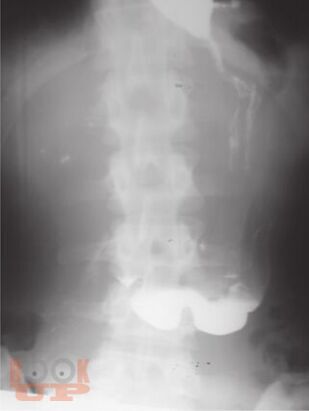

В основу издания положено собрание избранных клинических разборов, регулярно проводимых в ЦНИИ гастроэнтерологии. Многие из приведенных наблюдений являются уникальными, представляя собой либо клинический раритет, либо описание необычного течения давно известного заболевания, либо недавно описанное новое заболевание, прижизненный диагноз которого стал возможным благодаря внедрению новейших диагностических технологий. Особое внимание уделено и уникальным коррекционным вмешательствам.